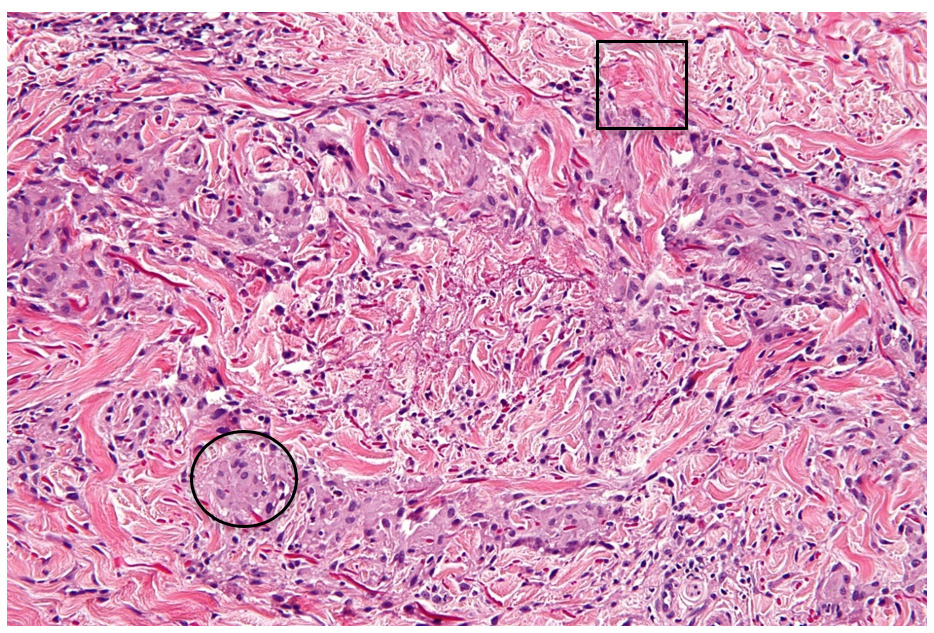

Patch GA may also appear similarly to a cutaneous lymphoma known as mycosis fungoides (MF), thus a skin biopsy becomes a vital step in proper diagnosis.13,14 Often used to evaluate tissue samples, hematoxylin and eosin (H&E) staining reveals unusual, or “atypical”, lymphocytes favoring the epidermis over the dermis (i.e., “epidermotropism”) in MF.13,14 This is different from patch GA, which shows macrophages (“histiocytes”) accumulating in the dermis, scattered around degrading collagen and blood vessels in an “interstitial” pattern, and/or surrounding decaying (“necrobiotic”) tissue in a “palisading” pattern.7,10,15

Contemplating the possible etiologies of this rash, the second author (MS) of this report obtained punch biopsies from a papule on her left posterior shoulder, a patch on her left flank, and a patch on her left thigh. All biopsies showed similar findings: a dense infiltrate of histiocytes forming palisading granulomas within the upper dermis. The epidermis did not show any atypical lymphocytes. Necrobiosis of connective tissue material was also appreciated (see Figure 3).

H&E staining is widely used when analyzing biopsy samples; it provides visualization of the various layers of the skin, its cellular components, and the tissue surrounding each cell (i.e., “extracellular matrix”).26,27 Hematoxylin is a basic, or cationic, dye that binds to negatively charged molecular components.26,27 Some examples include genetic material within a cell’s nucleus and ribosomes in a cell’s rough endoplasmic reticulum (RER).26,27 This dye appears “blue” on H&E and represents basophilic staining.26,27

Eosin, on the other hand, is an acidic, or anionic, dye and binds to positively charged molecular components.26,27 Examples most often include positively charged amino acids on intra- and extra-cellular proteins, such as organelles (intracellular) and collagen (extracellular).26,27 This dye appears “pink” on H&E and represents eosinophilic staining.26,27 Substances which are relatively neutral in charge, then, appear clearer on H&E, as in the case of extracellular mucin.26,27 Figure 4 shows an example of a granuloma annulare H&E stain to show these concepts.